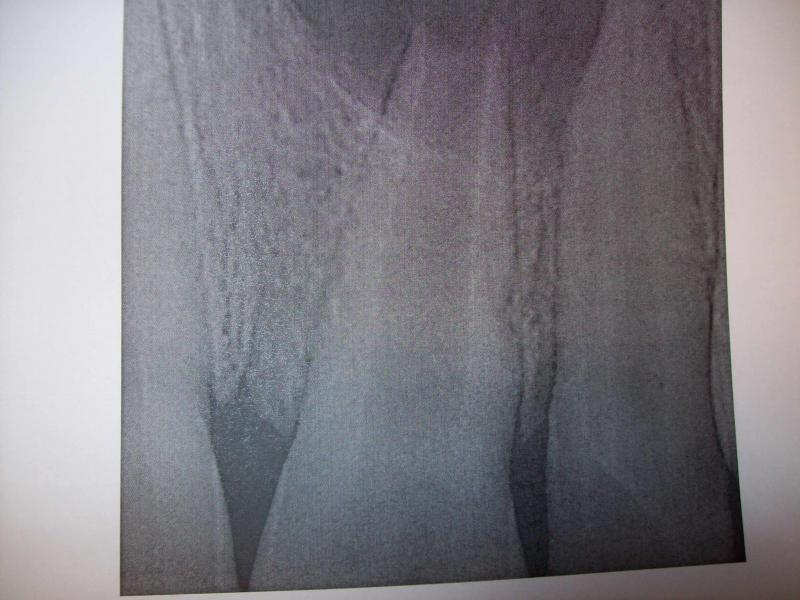

DR JET LOVES ROOT CANALS

General Dentist,  Performs Root Canals ONLY - Microscope Trained Dentist

"DR. JET'S MISSION IS TO PERFORM  ROOT CANALS FOR A REDUCED FEE USING THE LATEST TECHNOLOGY  AND TECHNIQUES TO SERVICE THE MANY PEOPLE WHO ARE UNINSURED OR UNDER-INSURED GIVING EVERYONE AN OPPORTUNITY TO SAVE THEIR TOOTH!"